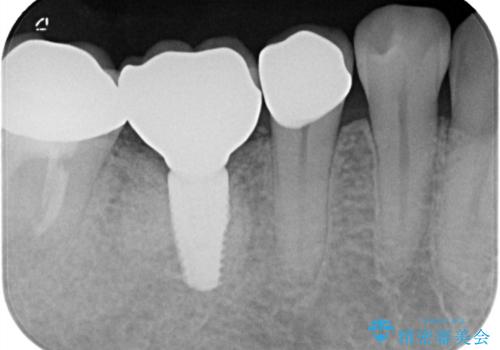

- 「食事をしていたら歯が欠けた」を主訴に来院された患者様です。

メタルインレーが入っており、インレーとの境の歯質が欠けている状態でした。

不幸中の幸いで欠けているところが根っこよりも上だったため、オールセラミッククラウンで治療を行いました。

銀歯を除去後、やはり銀歯の下は虫歯になっていましたので、虫歯を除去した後にオールセラミッククラウンで被せました。

MOD窩洞のインレーは破折強度が弱くたびたび今回の症例のように歯が欠けてしまうケースがあります。破折ラインが歯根までいっていると抜歯となってしまう場合もあります。

破折から歯を守る為にはインレーよりもクラウンの方が優れています。